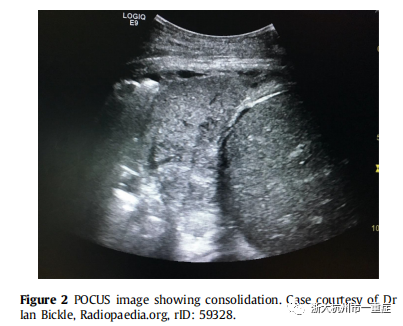

对于非COVID间质综合征患者的检查,超声的准确率(95%;敏感度98%,特异性88%)优于胸部X线(72%;敏感度60%,特异性100%)和听诊(55%;敏感度34%,特异性90%)。超声还能区分心源性与非心源性肺水肿,并能快速排除重症缺氧的其他原因。对于实变(Figure 2)超声的准确率为97%(敏感度93%,特异性93%),而胸部X线检查的准确率为75%(敏感度68%,特异性95%),听诊的准确率为36%(敏感性8%,特异性100%)。